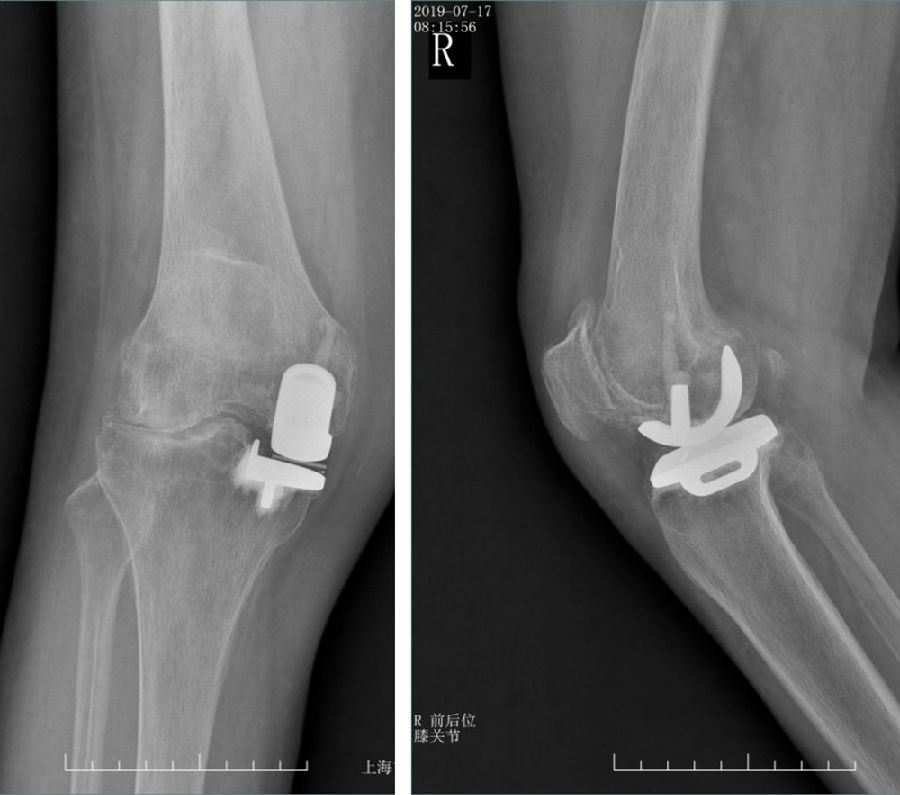

Case3:一期Bi-UKA治疗双间室OA

术前动力位片

术前透视。A.模拟负重位B.内翻应力位C.外翻应力位D.侧位

手术切口与暴露。A.膝前正中切口B.髌旁内侧入路C.内侧、外侧股骨髁磨损,ACL功能正常

内侧单髁置换。A.截骨完成B.安装内侧假体,等待骨水泥凝固C.假体安装完成

外侧单髁置换。A.按照外侧假体,等待骨水泥凝固B.内外侧单髁假体安装完毕C.切口及引流

术后透视。A.正位B.侧位

术后1周X-ray片

术后1周下肢功能